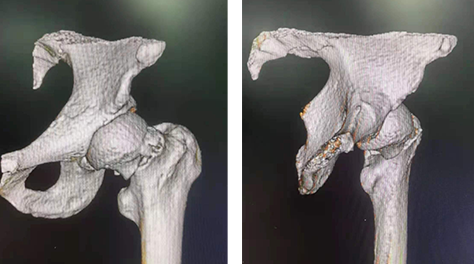

术前三维正位图(左)及侧位图(右)